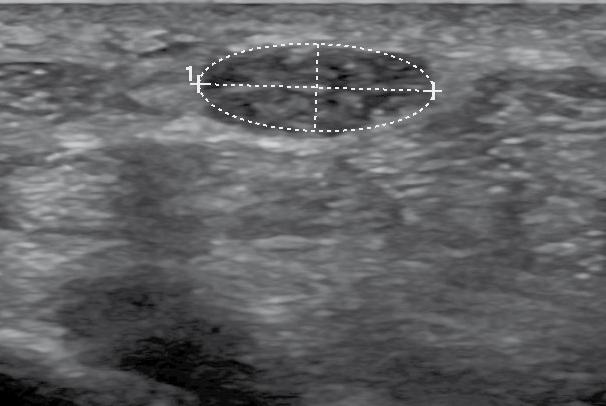

Infolge dauert es im Schnitt sieben Jahre, bis die korrekte Diagnose gestellt wird. Um auch bei aty pischen Symptomen an Endometriose zu den ken, braucht es Erfahrung. Die Anamnese hat einen sehr hohen Stellenwert in der Diagnostik und wird sehr umfassend erhoben. Ist die Ver dachtsdiagnose gestellt, muss eine Einschätzung der Ausbreitung erfolgen. Auch die gynäkologi sche Untersuchung geht über die eines RoutineCheck-Ups deutlich hinaus. Einen zunehmenden Stellenwert hat die Sonographie bekommen. Am Endometriosezentrum arbeiten wir mit moderns ten Ultraschallgeräten. Damit sind wir in der Lage, auch kleinste Endometrioseläsionen aufzudecken. Die Sonographie ist, sofern sie von EndometrioseExperten durchgeführt wird, gleich sensitiv und spezifisch wie eine MRI-Untersuchung.

Endometriose-Herde im Darm

In diesem Fall waren die Endometriose-Herde nur auf dem Ultraschall erkennbar, im MRI hin gegen nicht.

Ultraschall Foto von der Operation Makrofoto Pathologie

Unser aus zwei Gynäkologinnen und drei Gynäko logen bestehendes Endometriose-Team ist aus gebildet, im optimalen Fall die kleinen, einige Mil limeter grossen Herde sonographisch darstellen zu können. Bei der systematischen Untersuchung werden zudem nicht nur der Uterus und die Ova rien, sondern die komplette Umgebung der inne ren Geschlechtsorgane im kleinen Becken darge stellt. Dies beinhaltet die komplette Darstellung der Ligamenta sacrouterina, der Tuben, Urethra, Blase, Ureteren und die Rektum-, Sigmawand. Die Beurteilung der Darmwand hat eine beson dere Bedeutung, da bei vermutetem Darmbefall die präoperative Vorbereitung interdisziplinär mit den chirurgischen Kollegen stattfinden muss. Bei bestimmten Fragestellungen (z. B. Cavumform, Junktionalzone) kommt die 3D-Sonographie zum Einsatz. Bei der bimanuellen Untersuchung wird die Muskulatur im kleinen Becken beurteilt, um eine mögliche myofasziale Schmerzkomponen te auszuschliessen. Zudem wird die Reprodu zierbarkeit der Schmerzen überprüft. Wenn die anamnestisch angegebenen Schmerzen an be stimmten Lokalisationen ausgelöst werden kön nen, wird die Therapie-, und Operationsplanung deutlich einfacher.